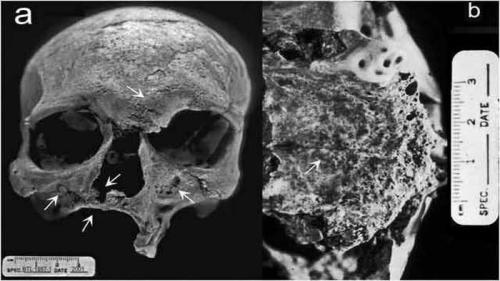

Первый прокаженный

Проказа, также известная как болезнь Хансена, не является заразной, но ее жертв часто изгоняли из общества, поскольку они были сильно обезображены. В Индии был найден череп кремированного человека, который считается первым прокаженным.